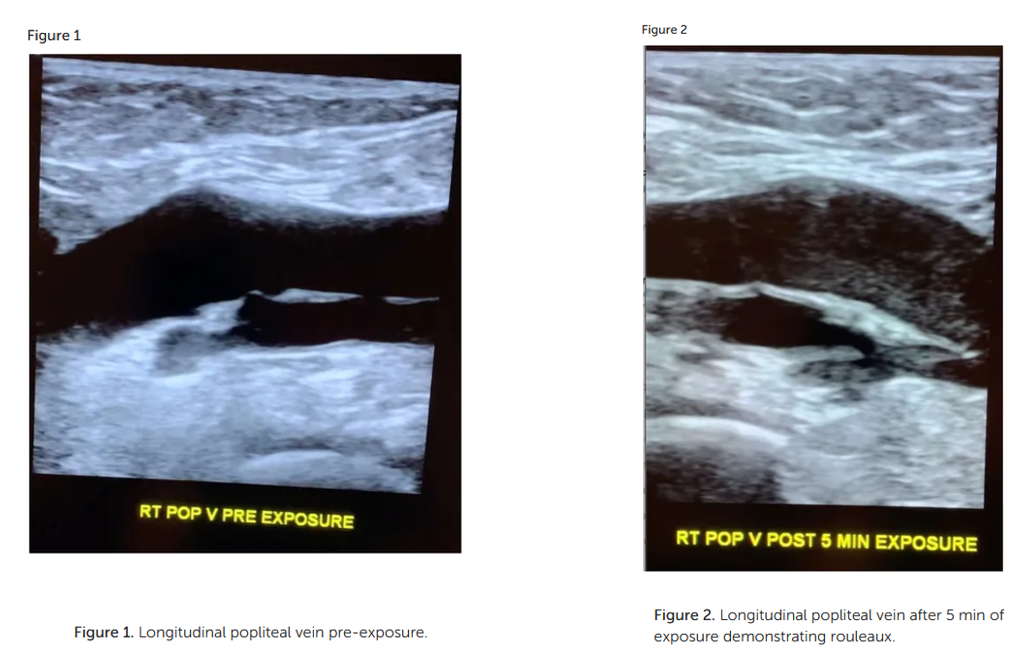

Smart Phone Exposure Shows Rouleaux Formation Via Ultrasound In Large Leg Veins Within Minutes And New Guidelines For Safe Exposure For Kids To Smart Devices - Age 0-6 No Screen Time Is Safe!